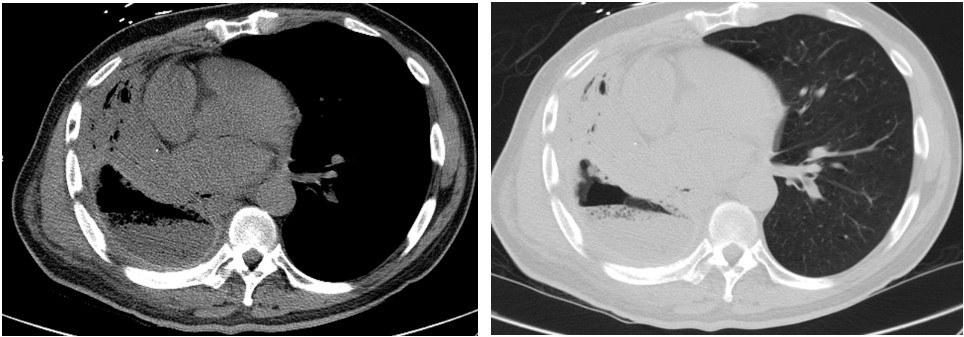

On evaluation, he was tachycardic with fever (38.6 °C) and exhibited decreased air entry to his RLL. Contrast enhanced Computed Tomography (CT) of the chest was done and showed right middle and lower lobe consolidation with areas of cavitation and a moderate right sided pleural effusion (Image 1). The patient was started on broad spectrum antibiotics. A repeat CT chest was obtained on day 7 due to clinical deterioration, which showed a new right-sided hydropneumothorax (Image 2). A pigtail chest tube was placed by Interventional Radiology that drained brown, markedly turbid fluid that was exudative based on Light’s criteria (pH < 6.3, LDH 575). His chest tube output continued to drain copious volume (average: 400 ml/day) of turbid, foul-smelling fluid with particulate matter over the next few days. Microbiological data identified polymicrobial growth of oral/upper respiratory tract: GPC in pairs and chains, GPRs, and candida glabrata. Subsequent CT chest after chest tube placement is shown below (Image 3):